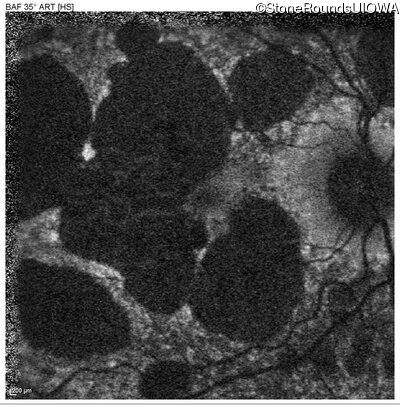

Blue Autofluorescence - Right - 20/20 -3

Exemplar

Blue Autofluorescence - Left - 20/40 +2